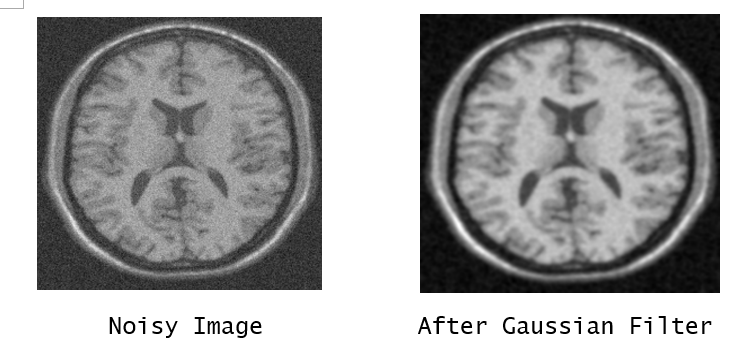

a. Gaussian Filter – Gaussian filter is a linear filtering process that is used to decrease the contrast and blur an image. By convolving the measured surface with a Gaussian weighting function, Gaussian filters may be applied to the input surface. A bell-shaped curve represents the Gaussian weighting function.

Refer to caption

Figure 4: